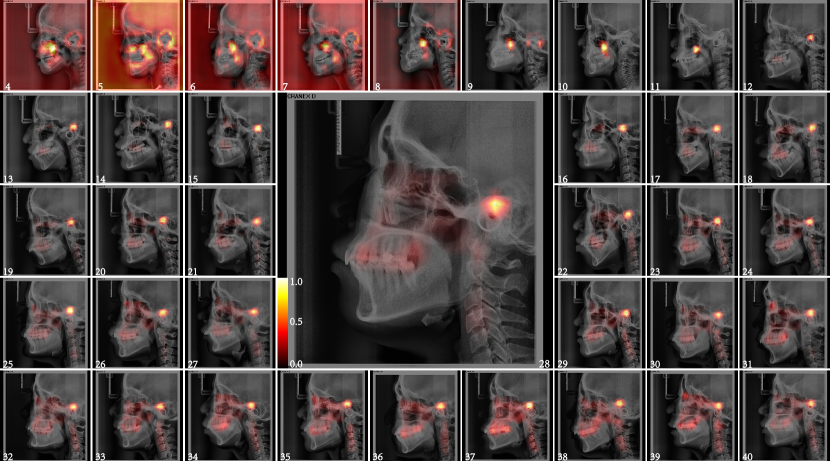

After the basic model was trained, saliency map is generated to observe the significance of each part in the LC image for age-estimation, which are shown in Fig.2.

We take each year as an age group and select the LC images whose estimated age is closest to the actual age, and the saliency maps are generated to determine the key areas of different age groups that are most closely related to age inference, as shown in Fig. 10 we have the following findings 1) Before the age of nine, the skull and maxilla showed a strong correlation, which was consistent with the development stage of the skull and maxilla. 2) At the age of 10-13, the maxilla, mandible, cervical vertebra and skull showed a strong correlation, suggesting that the craniofacial and cervical vertebra had a rapid development and change in puberty. 3) The saliency maps over 14 years old shows consistent salient area, which is divided into three areas, the tooth area, the cervical spine area and the craniofacial area without the teeth. 4) With the increase of age, the change trend of the salient area is increasing, which indicates that the more tissues in LC image undergone aging changes with age. 5) In the saliency maps over the age of 14 years, the most salient area related to age inference showed amazing consistency. It is located in the upper part of the external auditory canal. Due to the overlap of the left and right bone tissues of the LC image, we can not determine which part of the head the most salient area is. This requires subsequent 3D image research. The The average saliency maps of each year age group Fig. 11 can also well reflect the above findings.

The average saliency maps of each part were shown in Fig. 12, Fig.13 and Fig.14. The salient area of each part is consistent with that of the whole LC image. The location and shape of the salient area in the heat map of each year age group showed a high degree of consistency. The salient area of teeth part were mainly teeth and periodontal tissues, especially the upper posterior teeth, this should be related to the wear of the teeth and the ageing changes of the periodontal tissue.(Fig. 12) The salient area of the craniofacial part without the teeth were mainly midface(Fig.13). Many scholars have conducted in-depth research on the aging changes of the orbit, and the volume of the orbit increases with age. The development of the maxilla is also a research hotspot, but the research on the aging of the maxilla in adults has not been involved. The saliency maps reminds us that it is necessary to conduct aging research on other organizational structures in the middle of the face. The salient area of the cervical spine part were all of cervical spines and intervertebral disc in the LC image. The morphological changes of the cervical spine are used to determining the pubertal growth spurt of adolescence[27-29]. The cervical spine was also used to infer age and gender [30-32] , but it is mainly used for children and adolescents, there is no relevant research using the cervical spine to infer the age of adults. The cervical spine consists of 7 vertebral bodies and intervertebral discs. After the development is complete, the structural changes of the cervical spine begin in middle age, but sometimes earlier[33]. I ntervertebral disc degeneration begins at adolescence, and as it progresses, it can also leads to morphological alterations of the vertebral bodies. Cervical lordosis increased with age[34]. These changes are difficult to use by traditional methods of inferring age.